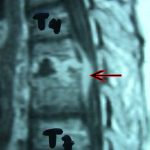

Εικ. 3: Μαγνητική τομογραφία της Θ.Μ.Σ.Σ. οβελιαία τομή, ακολουθία Τ1 & Τ2

Παρατηρούμε την αλλοίωση του σήματος σε όλες τις ακολουθίες, ενδεικτικό της ύπαρξης λοιμώξεως στο μεσοσπονδύλιο δίσκο και εκατέρωθεν αυτού στα σπονδυλικά σώματα. Είναι εμφανής η ύπαρξη επισκληριδίου αποστήματος στο σύστοιχο επίπεδο Θ5-Θ6 (ζ,η)